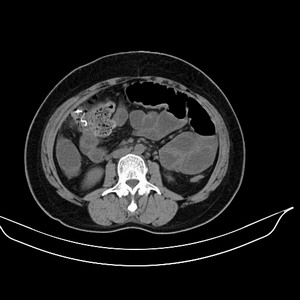

女 42岁 子宫肌瘤于外院术后两天,感腹胀。x线提示肠梗阻。

子宫肌瘤于外院术后两天,出现肠扭转梗阻,很明显。但右下腹部出现的线状高密度,是什么呢?有什么手术会有这样的物品呢?不会把电刀的导线遗留在腹腔吧!?

结果:术后纱布遗留,术后麻痹性肠梗阻肠梗阻

上面的图像是我们从手术室拿来的纱布做了个ct平扫,发现纱布里确实存在有一条致密影。后得知致密影是为防止手术时纱布遗留而设计。关腹时怀疑纱布遗留可做个床边透视或拍片可明确。